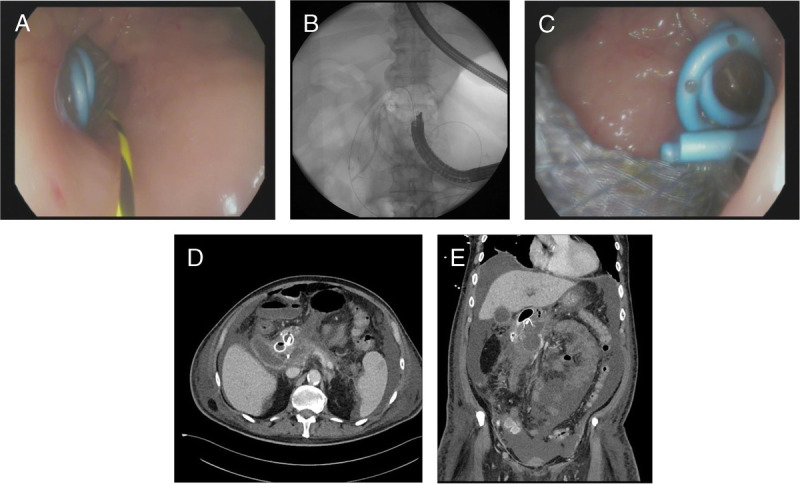

eus引导的介入治疗已成为广泛接受的胰周积液引流的治疗管理选择。除了内窥镜技术外,EUS介入还需要了解内窥镜支架置入技术并熟悉可用的支架和部署系统。虽然通常安全有效,但即使在专家手中,也可能发生正确支架定位的技术故障或严重的不良事件。在这篇文章中,我们讨论了跨壁eus引导支架置入中常见和罕见的不良事件,预防它们的方法,以及发生时的管理选择。了解可能出错的风险,结合临床专业知识、高水平的技术技能和充分的培训,可以确保eus引导引流手术的安全进行。与患者讨论手术风险及其可能性是同意过程的基本部分。

EUS-guided interventions have become widely accepted therapeutic management options for drainage of peripancreatic fluid collections. Apart from endosonographic skills, EUS interventions require knowledge of the endoscopic stenting techniques and familiarity with the available stents and deployment systems. Although generally safe and effective, technical failure of correct stent positioning or serious adverse events can occur, even in experts' hands. In this article, we address common and rare adverse events in transmural EUS-guided stenting, ways to prevent them, and management options when they occur. Knowing the risks of what can go wrong combined with clinical expertise, high levels of technical skills, and adequate training allows for the safe performance of EUS-guided drainage procedures. Discussing the procedural risks and their likelihood with the patient is a fundamental part of the consenting process.